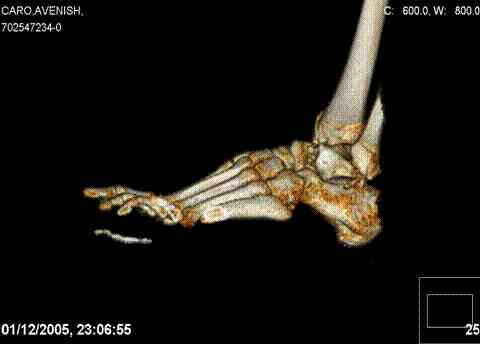

Re: Осколчатый перелом таранной кости

ya by popytalsya sobrat talus anatomichno,seichas pozdno operirovat iz za oteka,po etomy distrakziya apparatom budet optmalna.Posyalu vam podobyai moi sluchai.

14 years old girl

Fall from height ( 3rd floor)

Compressed fractures of L1-L2

Fx of orbital bone